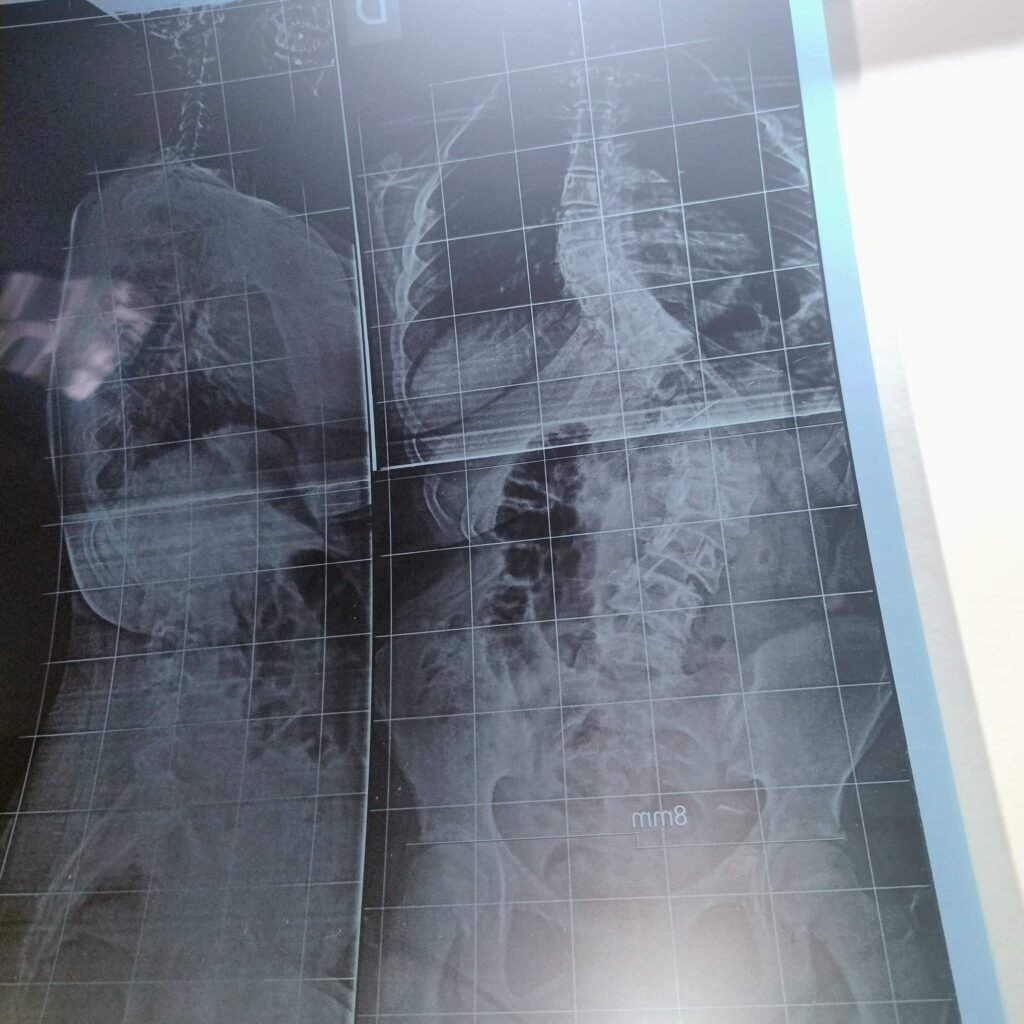

La afección fue detectada cuando Alessia tenía apenas tres años, a partir de una radiografía realizada por un broncoespasmo, donde ya se observaba una desviación en la columna. En ese momento, los médicos indicaron un seguimiento a la espera del crecimiento.

“La columna le mide 80 grados y tiene afectado el 60%. No hay otro tratamiento que no sea la operación”, explicó su padre, Nicolás Dell Acqua.